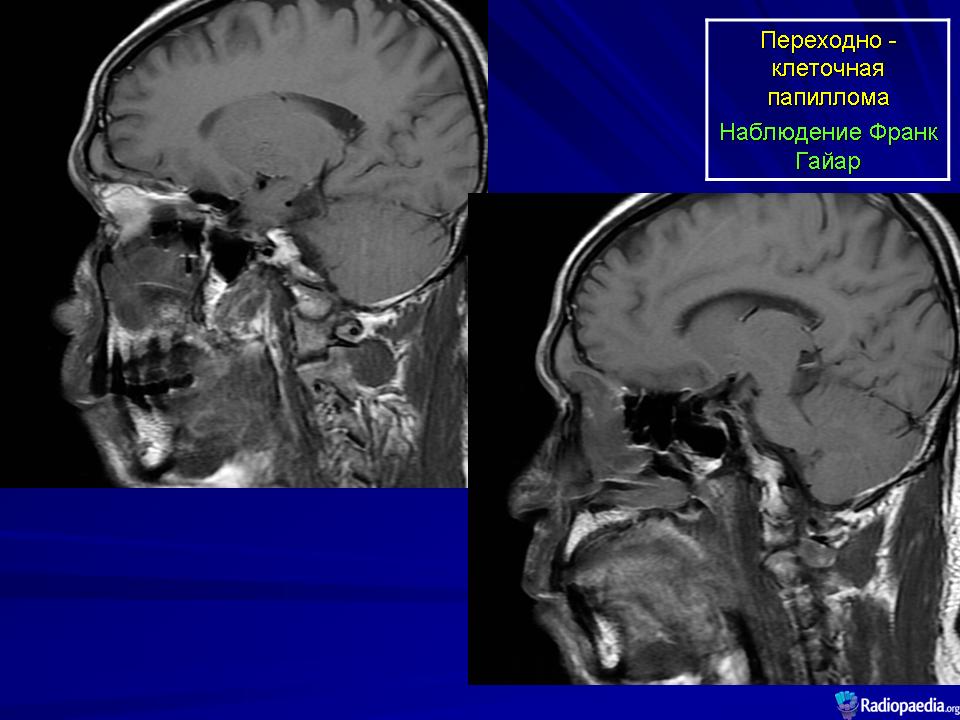

Переходно-клеточная папиллома.

Инвертированная переходно-клеточная папиллома (син.: папиллома Шнейдера, эпителиальная папиллома, сосочковая фиброэпителиома, папиллярный синусит, цилиндроклеточная папиллома, папиллома из респираторного эпителия) — редкая, но характерная для полости носа и его синусов доброкачественная опухоль, составляющая около 0,5 % от находок всех новообразований носа. Она чаще встречается у мужчин, преимущественно на пятом-шестом десятилетии жизни. Обычно односторонняя, эта опухоль бывает одиночной и множественной. Как правило, она возникает на боковой стенке полости носа, а также в околоносовых пазухах: гайморовой полости, решетчатом лабиринте, изредка в лобной и основной пазухах. При сочетанном поражении локализацию первичного узла установить практически невозможно. Из полости носа опухоль может врастать в околоносовую пазуху и наоборот. Пациенты обычно жалуются на заложенность носа, выделения, носовые кровотечения, боль в области лицевого нерва. Иногда в зоне опухолевого роста происходит разрушение костной ткани. Чаше всего страдают стенки гайморовой пазухи. Но опухоль может расти и в других направлениях, разрушая стенку неба, стенки глазницы или кости основания черепа. Рецидивы опухоли могут возникать через 5—10 лет. Примерно у 5% больных инвертированная переходно-клеточная папиллома способна превращаться в рак после долголетнего доброкачественного течения. Метастазы не наблюдаются.

Макроскопически мягкая, со складками, опухоль имеет дольчатое, сосочковое строение, шероховатую поверхность. Цвет ее ткани варьирует от розового до желто-красного. Инвертированная переходно-клеточная папиллома рецидивирует в 75 % случаев, если проведена локальная эксцизия. Для оптимального лечения при локализации опухоли на боковой стенке носовой полости рекомендуется боковая ринотомия и срединная резекция верхней челюсти. Если такая папиллома малигнизируется, то ее клиническое течение становится более агрессивным.